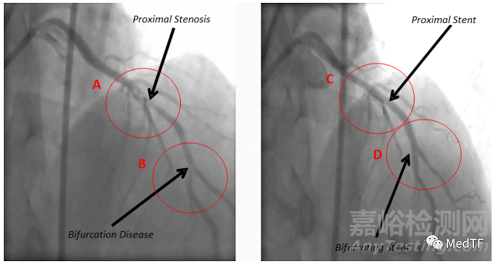

ABS已經(jīng)完成多例臨床試驗(yàn),以下是其中一個(gè)病例影像:

圖中圓圈 A 處為近端變窄或狹窄,圓圈 B 處為分叉病變

下圖顯示了閉塞的血管,并且顯示了植入后的血管恢復(fù)了良好的血流。ABS在大約 5 分鐘內(nèi)部署完畢,并在部署前直接穿過(guò)另一個(gè)支架,無(wú)需預(yù)擴(kuò)張。